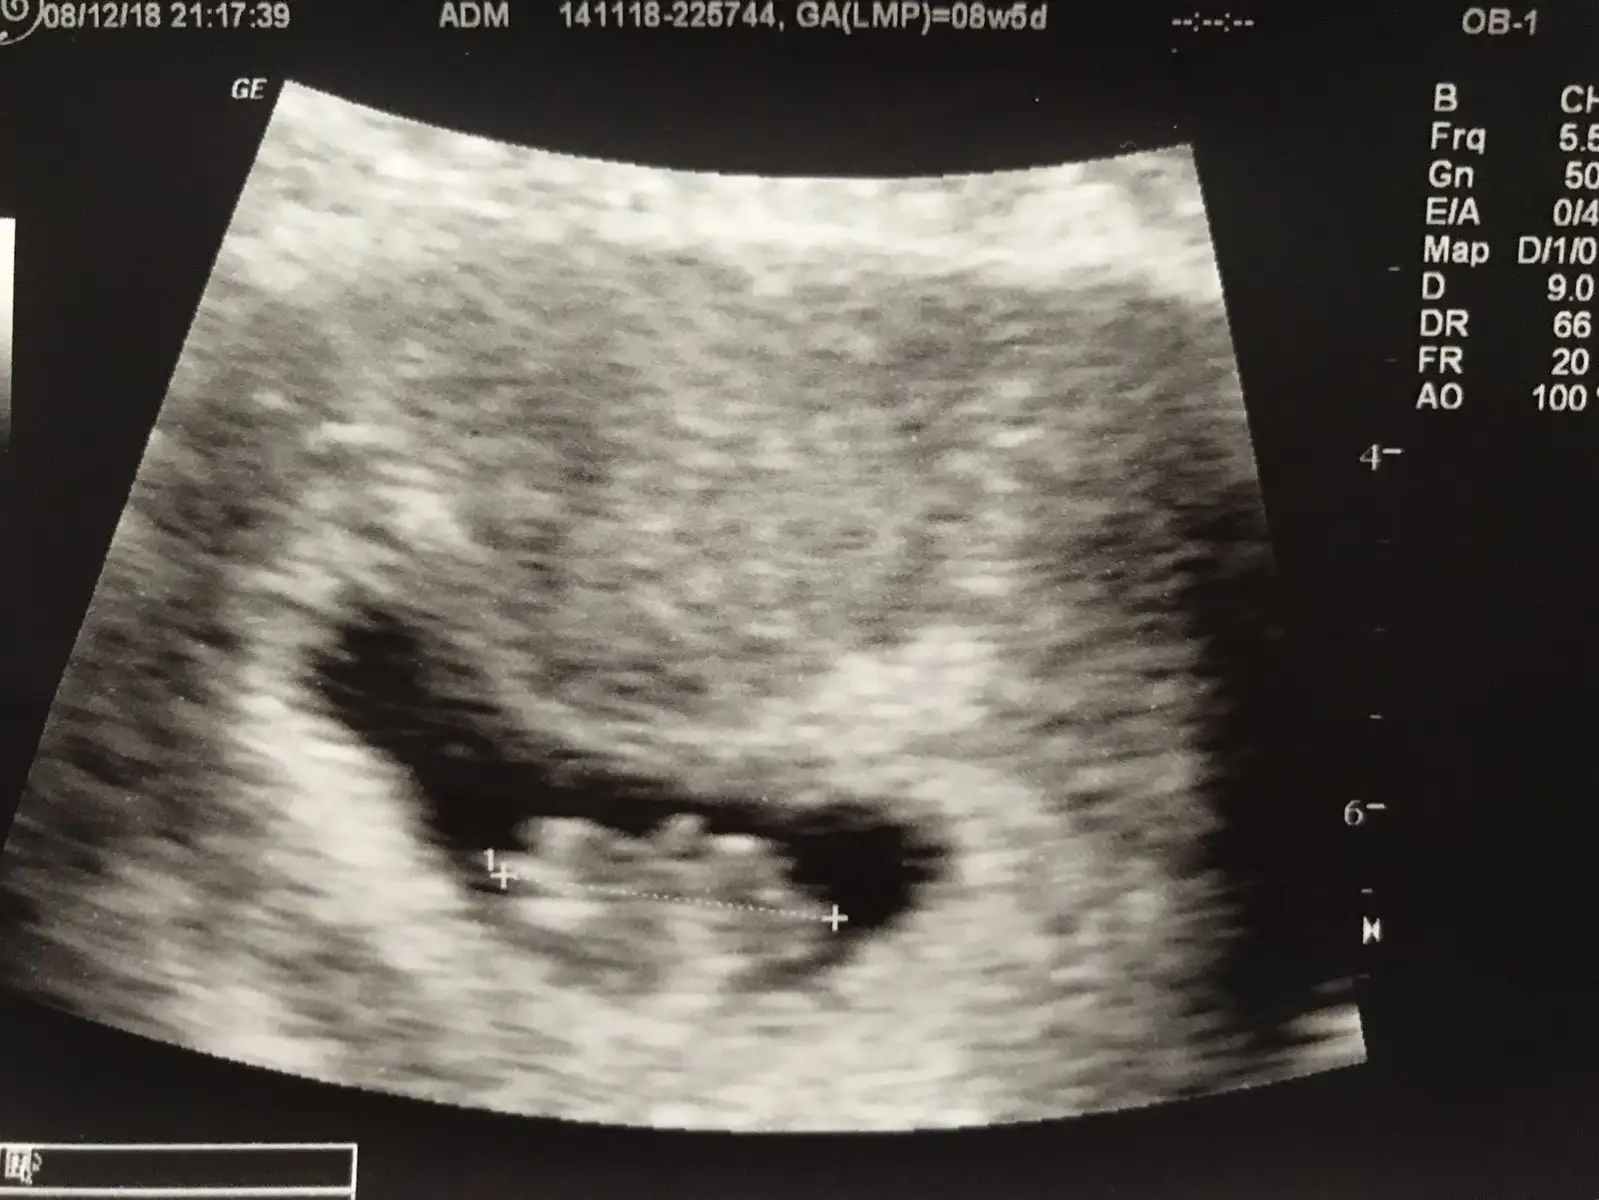

Hemen umutsuzluga kapilma bak dha 6 haftalik diyorsun bebek muhtemeln gec dollenme olmustur o yuzden duyulmamıştır uzme kendini de bebisini de canim gun dogmadan nelrr doğar herkesin ayni olmayabiliylr herkes aynı haftada duymayabliyor sn stres yapma dua et melegin icin tatlim dualarim seninleKahve rengi lekenmem vardı kızlar geçti ama leke felan yok sata göre 7+2 yim kese normal bebek 6 haftalık görünüyor dedi kalp atşı hareketi görmedi duymayı bırakın haftaya kadar bekleyelim dedi inşşah canlanır ama benimde umudum kalmadı

Maşallah kuzum oynadı mı :)merhaba kızlar bugun kontrolum vardı 8+5 masAllah kuzum ıyıymıs 8+2ymıs gelısım olarakta.